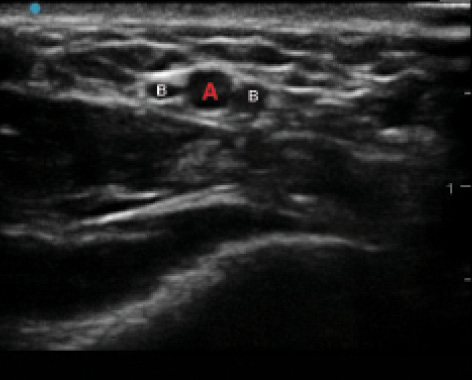

US guidance is useful in instances where the radial artery is difficult to localize by means of palpation. A high-frequency linear transducer is the probe of choice (eg, 13-6 MHz). Color Doppler can be helpful if the artery is not easily identified by pulsation alone, but it is often unnecessary. We recommend a short-axis, out-of-plane approach (Figure 2) because a long-axis view of the radial artery is difficult to reliably achieve given the small vessel diameter. Many novice users of US have difficulty visualizing the tip of the needle during an out-of-plane approach. As a result, it is often difficult to judge the depth of the needle, making single-wall puncture challenging. There are two simple solutions to this problem: (1) ask an assistant to constantly visualize the hub of the needle and alert the provider when flash is obtained, or (2) utilize a transfixation technique during US-guided access so that needle depth is not a primary concern.

Figure 2. A short axis US image of the distal radial artery (red A). The artery is accompanied on both sides by radial venae comitantes (white Bs).